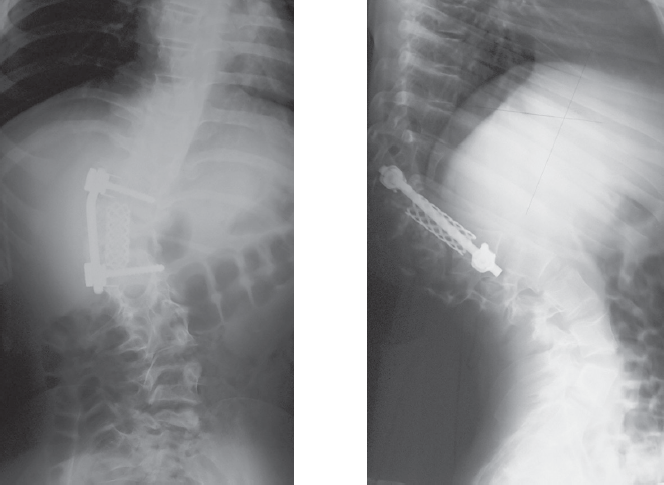

Наложено краниофеморальное скелетное вытяжение. За 35 суток достигнута коррекция сколиотической деформации на 17° (32 %), кифотической — на 12° (14 %). Учитывая расположение правого мочеточника в зоне доступа к телам позвонков грудопоясничного перехода, непосредственно перед основным этапом оперативного лечения под контролем флюороскопии в мочеточник заведен стент. В положении на левом боку выполнена торакофренолюмботомия через ложе 12-го ребра. Отмечено снижение высоты межпозвонковых дисков, отсутствие пульпозных ядер на вершине деформации, конкресценция тел Th12 и полупозвонка L1. Дискэпифизэктомия в парах Th11-Th12, L1-L2, L2-L3, спондилодез сульфатом кальция в комбинации с аутогенной костью (резецированное ребро). Между телами позвонков Th11 и L3 установлен сетчатый имплант Mash. Через тела позвонков Th11 и L3 бикортикально проведены винты, коммутированы стержнем. Плевральная полость и забрюшинное пространство дренированы. Рана послойно ушита. На 12-е сутки после операции больная вертикализирована в корсете. Через 5 месяцев госпитализирована для контрольного обследования и проведения заключительного этапа хирургического лечения. По данным рентгенографии, достигнутая коррекция сохраняется (рис. 5). В качестве заключительной операции выполнен задний спондилодез на вершине деформации.

Рис. 5. Рентгенограммы через 5 месяцев после операции